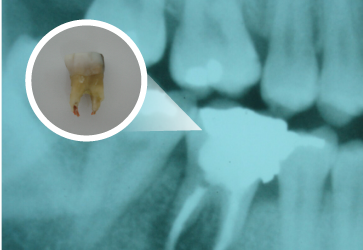

Reabsorção Dental

É a perda de tecido mineralizado em qualquer ponto da superfície radicular nos dentes

podendo ser externa quando inicia-se na superfície radicular externa e interna quando

iniciando nas paredes da cavidade pulpar.

Identifica-se uma reabsorção radicular através de exame de raio – x.